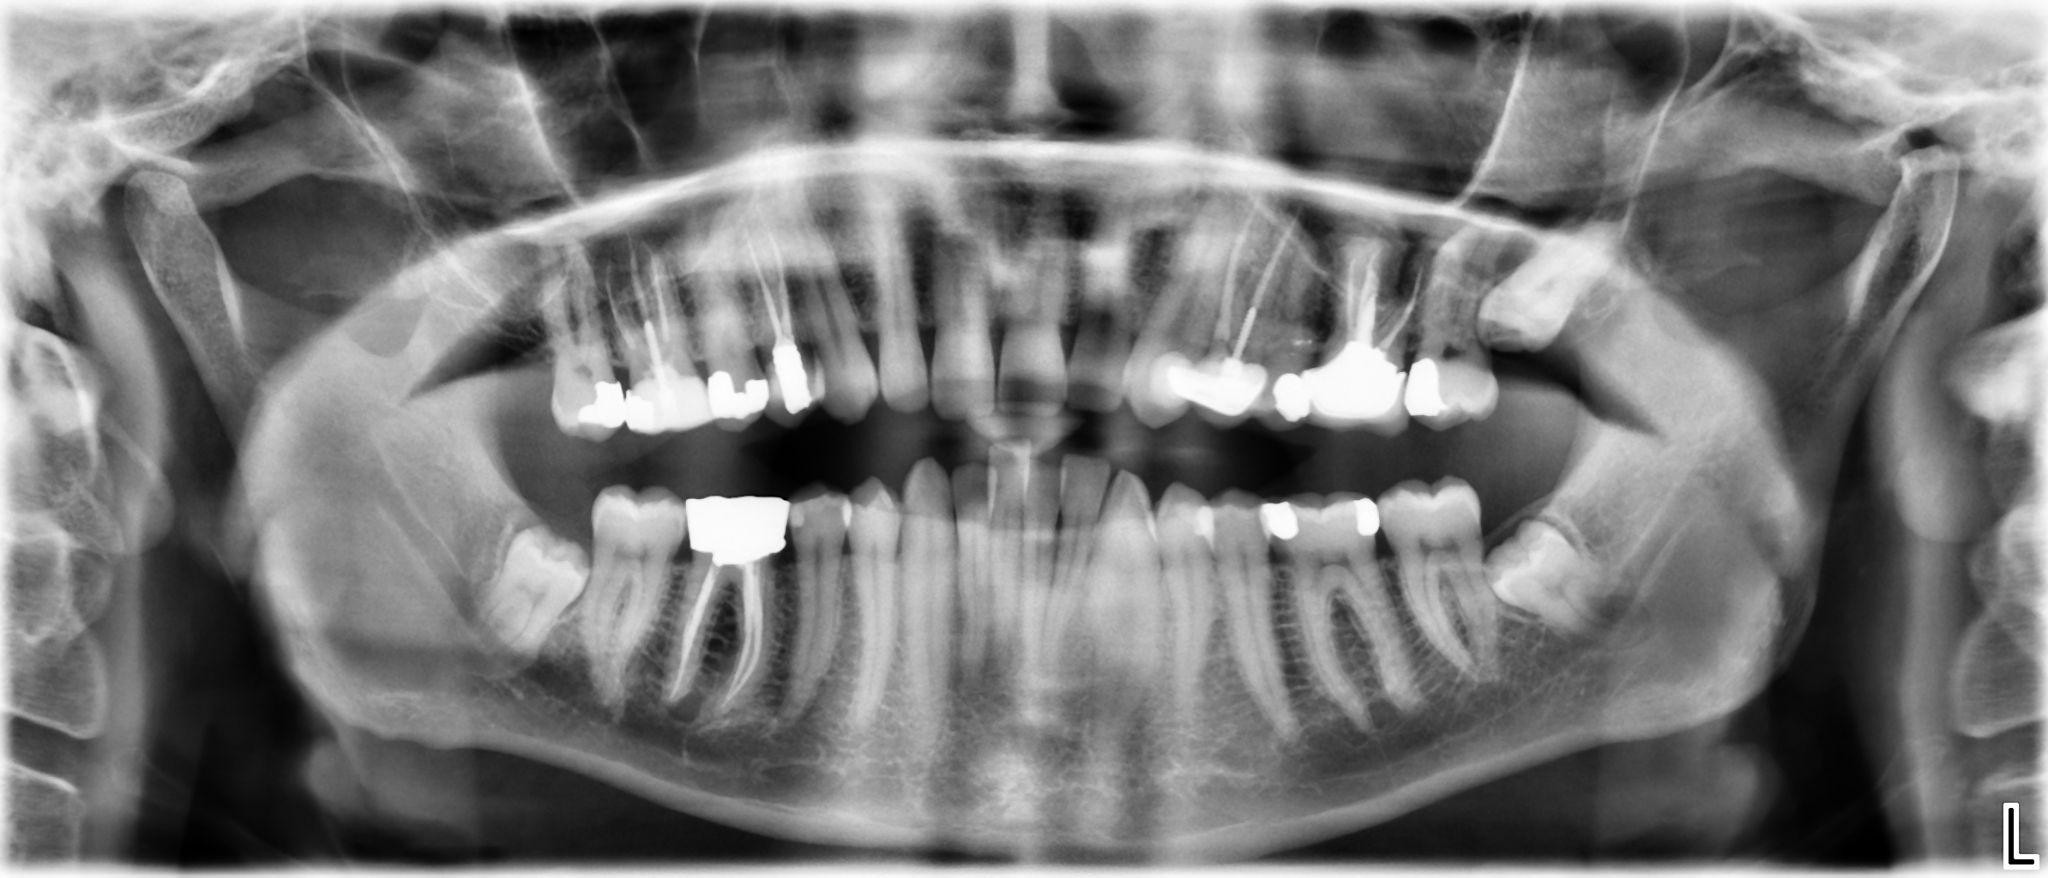

17. What options can be selected for the first quadrant of this panoramic X ray?

18. What options can be selected for the second quadrant of this panoramic X ray?

19. What options can be selected for the third quadrant of this panoramic X ray?

20. What options cannot be selected for the forth quadrant of this panoramic X ray?

21. What options can be selected for the first quadrant of this panoramic X ray?

22. What options cannot be selected for the second quadrant of this panoramic X ray?

23. What options can be selected for the third quadrant of this panoramic X ray?

24. What options can be selected for the forth quadrant of this panoramic X ray?